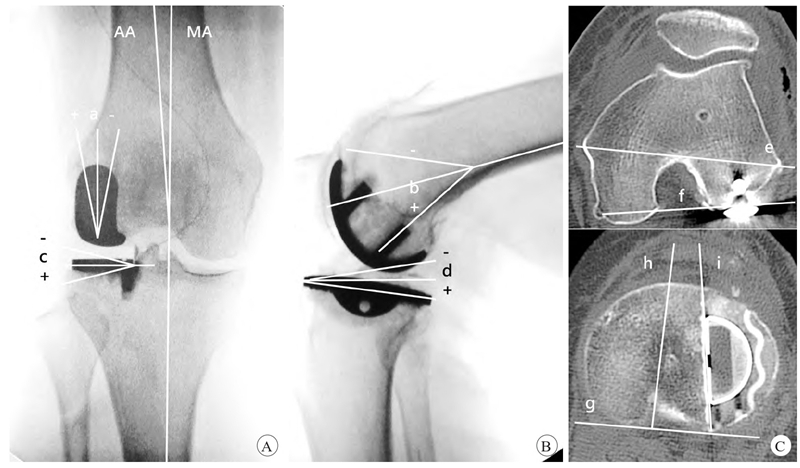

常规X线检查包括站立位正侧位、双膝站立位Rosenberg位和内外翻应力位X线检查。下肢力线评估通过股胫角(femor-tibialangle,FTA)在负重位X线片上测量整体下肢力线,以股骨和胫骨的解剖轴线的交角进行评估(图1)。UKA假体冠状位及矢状位力线评估需拍摄统一标准的X线片,即膝关节置于标准中立位:屈膝20°、下肢适度内旋、髌骨朝向正上方、不向内外倾斜。侧位X线片拍摄时放射片盒紧贴患膝外侧,与之平行,无任何旋转或内外翻。三维CT扫描评估假体旋转力线。具体方法参见图2。

图2 UKA假体力线测量方法示意

A.冠状位假体力线(a为股骨侧,+为外翻,−为内翻,c为胫骨侧,AA为解剖轴,MA为机械轴);B.矢状位假体力线(b为股骨侧,+为后倾,−为前倾,d为胫骨侧);C.假体旋转力线(e为股骨内外上髁连线,f为外侧后髁股骨假体力线,e、f夹角为股骨假体旋转角,−为内旋,指f线相对于e线内旋,+为外旋,指f线相对于e线外旋,g为胫骨平台后缘切线,h为胫骨平台前后轴,i为胫骨假体的外侧缘,h、i夹角为胫骨假体旋转角,−为内旋,指i线相对于h线内旋,+为外旋,指i线相对于h线外旋)。